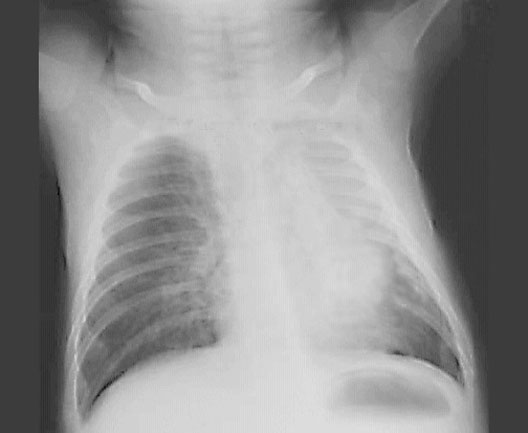

Child's Collapsed Lung

*Arrows point to collapsed lung.